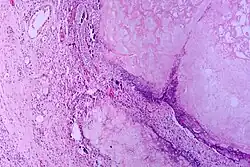

Tissue necrosis in chronic pancreatitis[9]